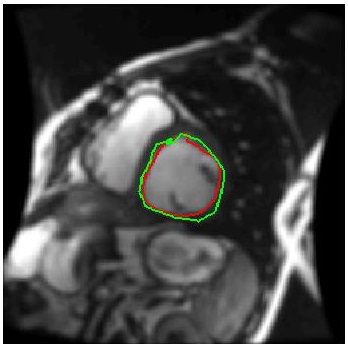

We train our ISR network from scratch. Each volume slice is treated as a separate image and transformed by random rotation and translation. We rotate the images between in steps of . For each rotation we translate the image by pixels in steps of . Thus on an average we get transformation for each image. Thus an average of slices per image gives a total of cardiac MR images. We show results on ISR for scale factor . Results for ISR are summarized in Tables 5. Following the approach for retinal landmark and pathology segmentation, we also show results for cardiac left ventricle segmentation (Table 6). For each segmentation approach we employ UNets as the segmentation framework and show results for different super-resolution methods as well as the low-resolution images (). Dice metric values for segmentation accuracy are shown in each case. Similar to retinal pathology segmentation we extract a patch covering the pathology and apply super-resolution for scale factors .

Figure 6 shows results for segmenting the cardiac LV from MRI. For each case we present results on the original HR images, SR images obtained by each of the methods being compared and also when using the LR images (scale factor ). It is quite obvious that the LR images are very fuzzy and don’t give accurate information on the anatomical boundaries. On the other hand the SR images from our method can predict a highly accurate reconstruction of the actual image. Other ISR methods show some degree of blur in the SR images. It is remarkable that deep neural network based methods are able to reconstruct original high quality images despite limited information in LR images. This is possible because of the ability of the generator networks to learn the relation between HR and LR images.